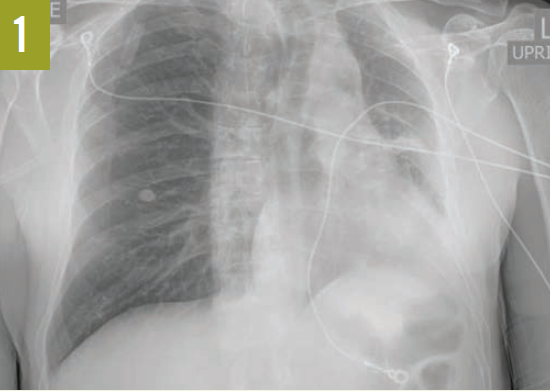

Upon admission, a chest radiograph revealed hyperlucency of the right hemithorax with a right basilar infiltrate (Figure 1). Computed tomography (CT) of the chest showed extensive unilateral bullous emphysema involving the entire right lung from apex to base (Figure 2). The emphysema was confined to one side and was so severe and voluminous that the mediastinum was pushed far away from its midline alignment with the sternum into the left hemithorax, resulting in compression and atelectasis of the left lung. There was also a right-sided pneumonia superimposed on the background of emphysema.

Figure 1. A chest radiograph showed hyperlucency of the right hemithorax and a right basilar infiltrate.